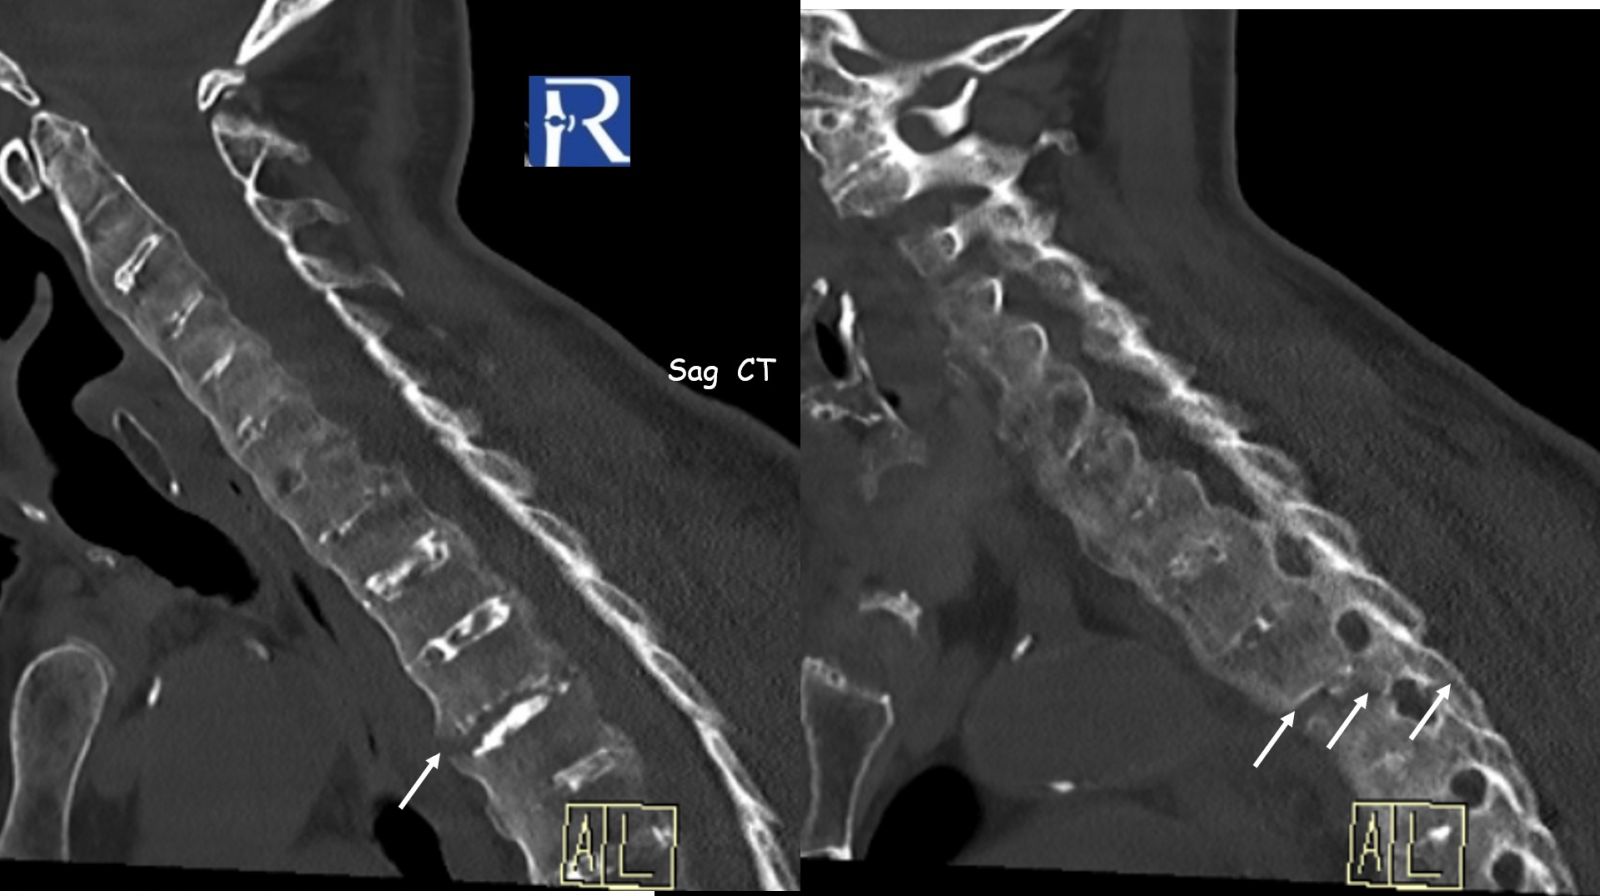

Imaging Findings

- Extensive bridging syndesmophytes throughout the spine

- Complete spinal ankylosis (“bamboo spine” morphology)

- At the T3–T4 level, a transdiscal fracture is observed

- Fracture line extends:

- From anterior fused syndesmophyte

- Through the intervertebral disc

- Into the posterior elements (facet joints)

This represents a classic “chalk-stick fracture”, a transverse fracture through a rigid, ankylosed spine.

3. Look beyond plain radiographs

- CT (especially sagittal reconstructions) is essential